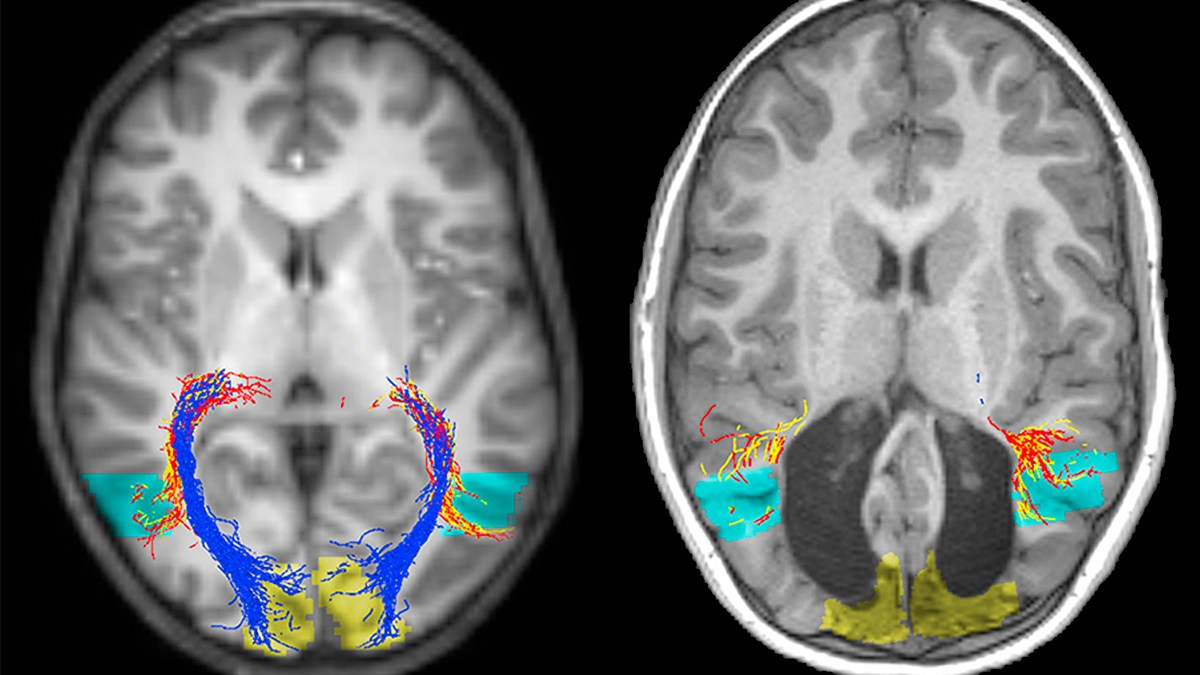

Credit: Inaki-Carril Mundinano, Juan Chen, Mitchell de Souza, Marc G. Sarossy, Marc F. Joanisse, Melvyn A. Goodale, James A. Bourne.

The scientists studied the unusual case, hoping to understand what makes B.I.’s condition so unique. Through MRI-scanning they found a remarkable instance of the brain’s neuroplasticity, with the boy’s visual pathway of neural fibers in the back of the brain enlarged. This adaptation means that the pathway allows the boy to see by doing the work of the visual cortex.